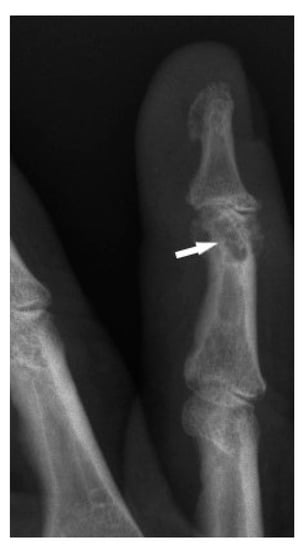

Bone sarcoidosis was first described in 1903 by Kreibich as the image of lace in the phalanges of the hands and this is considered the classic presentation of small bone involvement [8].

The typical cystic X-ray pattern of bone sarcoidosis was described for small bones of the hands only (Figure 1). Other skeletal sites of sarcoidosis evaluated by this modality may be a diagnostic challenge, showing no typical radiologic features of the disease. Increasingly used modern diagnostic methods such as MRI and PET-CT indicate that multifocal bone lesions are sometimes undetectable on X-ray [10,11,12].

Figure 1. X-ray of the finger. Sarcoidosis. Cystic lesions in the middle phalanx head (white arrow).